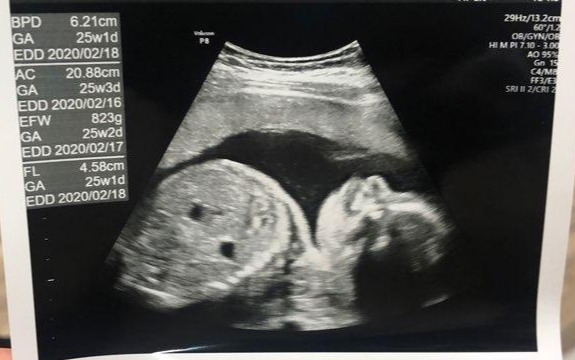

휴가 전 아내는 서류도 떼고, 꾸꾸도 확인할 겸 병원에 갔다. 담당해주시던 분이 없어서 다른 분의 진료를 봤는데, 첫마디가 ‘생각보다 크네요?’였다고 한다. 블루베리만 하던 꾸꾸는 어디 가고, 생각보다 큰 아기가 되었는가. 크기는 나를 닮지 않아도 되는데... 닮지 말았으면 하는 것만 닮는다는 인체의 신비가 꾸꾸에게도?

_이제는 한 장에 다 담기지 않는 아기가 되어버렸다